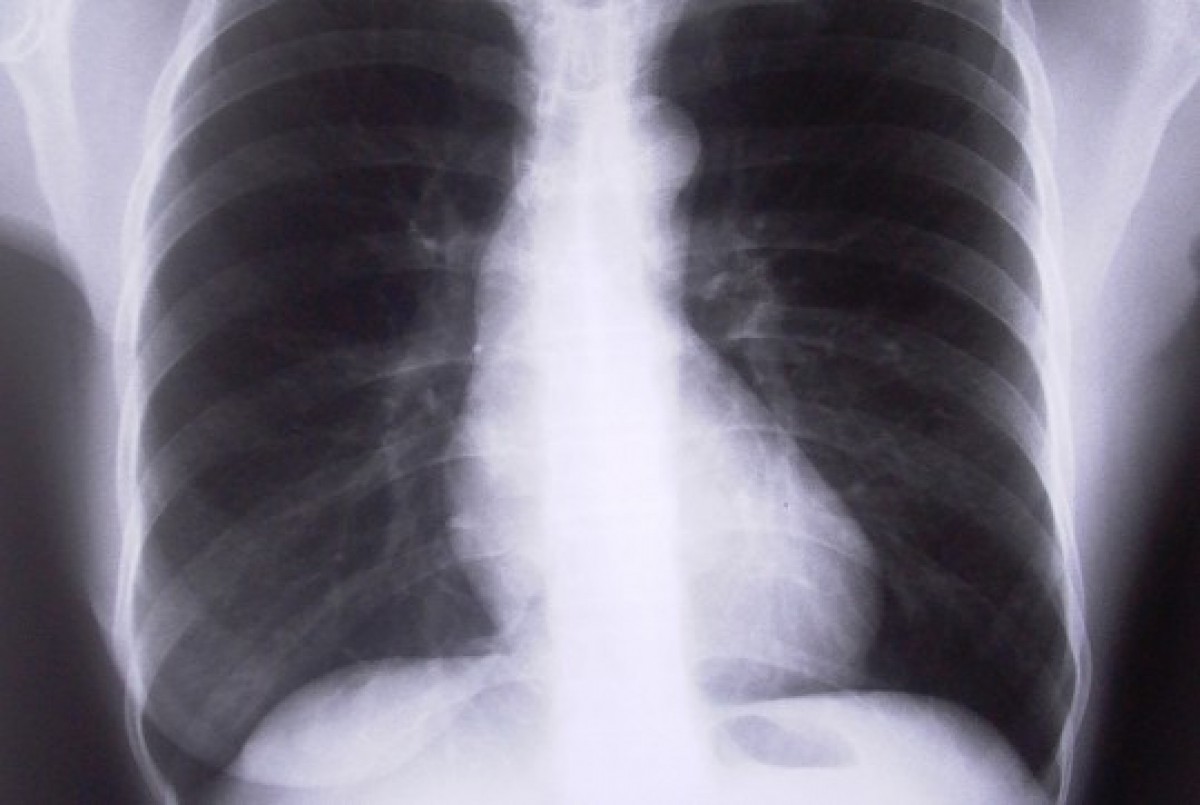

Ar šodienu arī plaušu digitālā rentgenogrāfija, kā arī citi rentgena izmeklējumi pacientiem ir pieejami jaunajā poliklīnikas ēkā Raiņa ielā. Tas joprojām ir maksas pakalpojums, taču poliklīnikas vadība strādā, lai rentgena izmeklējumiem piesaistītu valsts finansējumu.